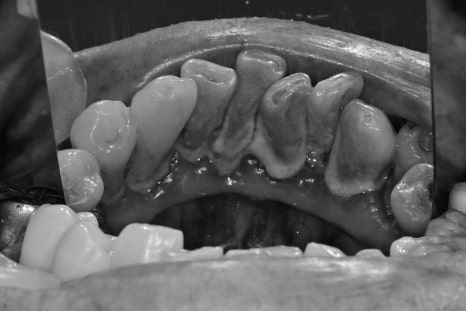

구강 내 사진을 보게 됐을 때

정상 잇몸 레벨에서 치은염의 진행으로 잇몸이 많이 내려앉은 상태에서

더욱 깊게 양치가 어렵다 보니 치주염으로 이미 진행이 된 상태였습니다.

전반적으로 스케일링과 치주치료를 진행한 후 사진입니다.

이미 내려앉은 잇몸은 다시 채울 순 없지만 더 이상의 염증의 진행을 막고

부어있던 잇몸을 가라앉혀야 임플란트나 다른 치료들이 예후성이 좋아집니다.